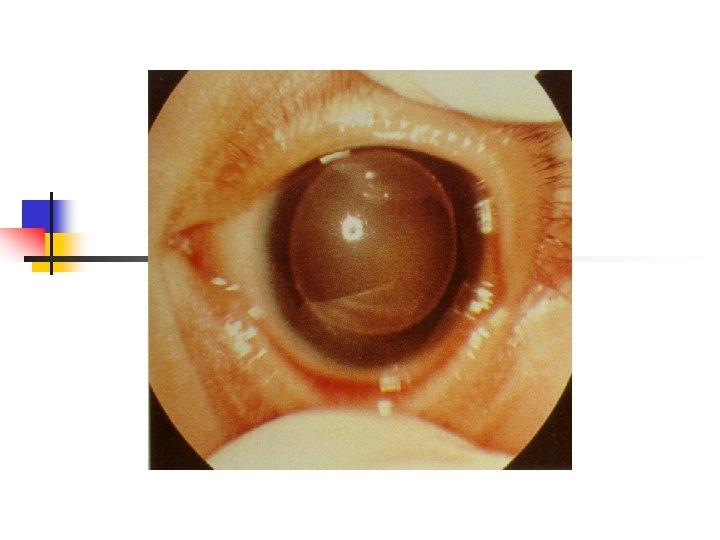

Genetic Syndromes n n n WAGR-WT, aniridia, genitourinary malformation, mental retardation; somatic germline deletions of 11 p 13 Denys-Drash-pseudohermaphroditism, severe glomerulopathy, WT; inactivating point mutations in the WT 1 gene, 11 p 13 Beckwith-Wiedemann-hemihypertrophy, macroglossia, omphalocele, visceromegaly; loss of heterozygosity in 2 nd WT locus on 11 p 15